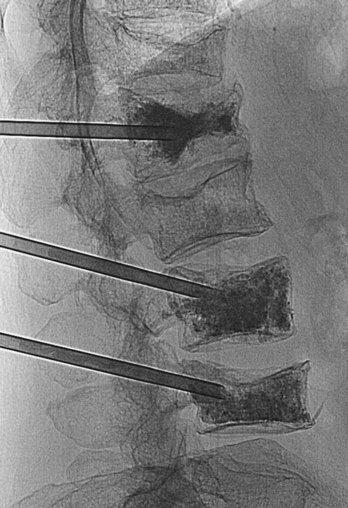

In the clinic Osteoporosis

Osteoporosis is a disease in which the bone mineral density is significantly reduced. This renders the bone significantly more at risk of fracture. Typically, osteoporotic fractures occur in the femoral necks, the vertebra, and the wrist. Although osteoporosis may occur in men, especially elderly men, the typical patients are postmenopausal women. There are a number of risk factors that predispose bones to develop osteoporosis. These factors include poor diet, steroid usage, smoking, and premature ovarian failure. Treatment involves removing underlying potentiating factors, such as improving diet and preventing further bone loss with drug treatment, (e.g., vitamin D and calcium supplements; newer treatments include drugs that increase bone mineral density) (Figs. 1.17 and 1.18).

image

Fig. 1.17 Radiograph of the lumbar region of the vertebral column demonstrating a wedge fracture of the L1 vertebra. This condition is typically seen in patients with osteoporosis.

Fig. 1.18 Radiograph of the lumbar region of the vertebral column demonstrating three intra-pedicular needles, all of which have been placed into the middle of the vertebral bodies. The high-density material is radiopaque bone cement, which has been injected as a liquid to set solid.